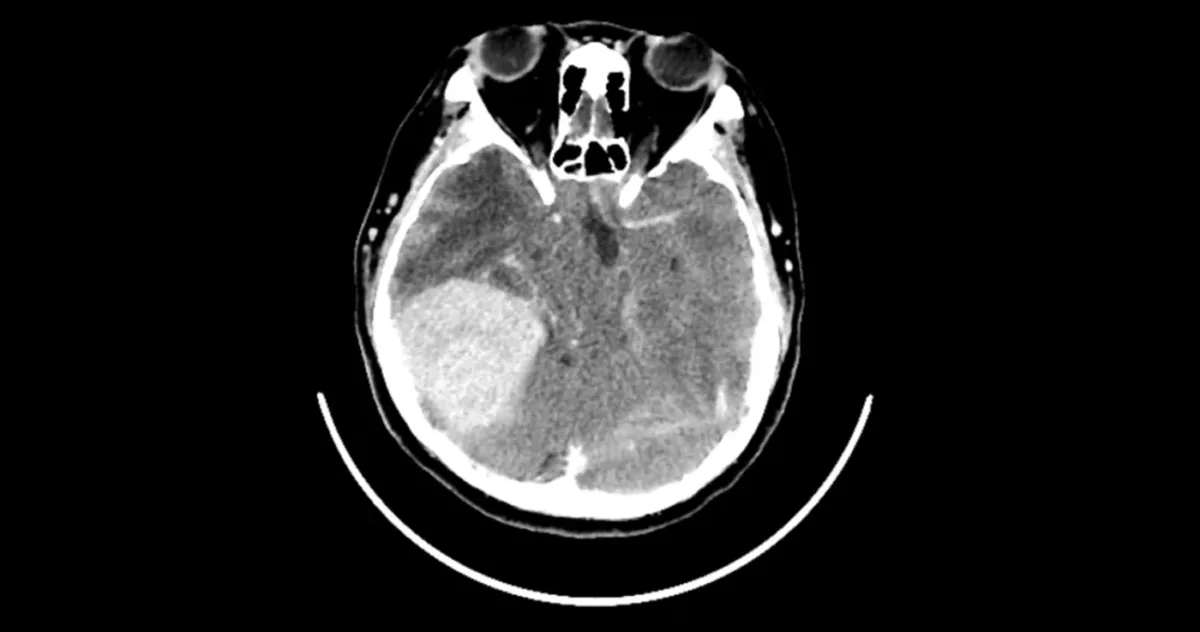

După o oarecare rezistență din partea spitalului (având în vedere lipsa simptomelor fizice), cererea a fost acceptată. Scanarea a scos la iveală ceva uluitor: o masă compatibilă cu un meningiom de dimensiuni mari, adică o tumoare pe creier. În ciuda lipsei aparente a simptomelor clasice, precum dureri de cap severe sau tulburări de vedere, echipa medicală a sugerat că intervenția chirurgicală era cea mai bună soluție, iar formațiunea a fost îndepărtată cu succes.